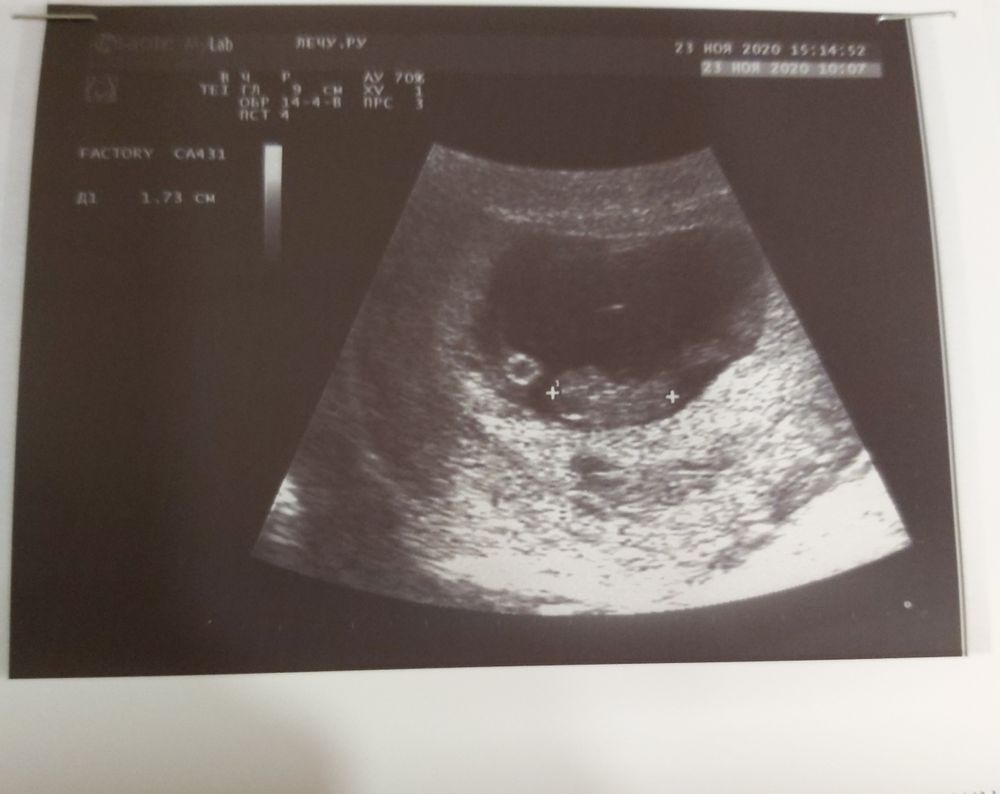

Сегодня была на узи, сердечко бьётся, колобочек один сидит. И по методу Рамзи девчонка🙈😂😂😂. Ну мы и не сомневались. Но пока надежда ещё есть.

Аня привет, ты знаешь мы оказывается не правильно рамзи расшифровываем, именно по этому фото у тебя по рамзи мальчик

Оль, я уже не верю ничему. Вот смотри моё узи в 6.5 это одно узи, только разные ракурсы.

Я видела, но по тому фото не понятно где плацента, Аманда сотней смотреть, а не по хориону

Вы молодцы рискнули. По Рамзи у вас мальчик, если вагинальный датчик был🙈.

Датчик вагинальный, врач сказал прикрепление по передней стенке слева, я тут пересмотрела фото, так и не поняла как определяете)))

НЮША (ник в ИГ Visla79), а если хорион справа, то кто? Врач вроде сказал, что справа прикрепился) Запуталась я с этим Рамзи и никак понять не могу. Вот кто у нас? Датчик наружний